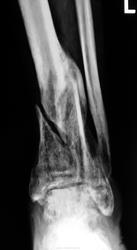

Как то странно-в стационаре лечение гипсом!!! Формируется "ложняк" и укорочение, очень жаль человека. И зона -очень неблагодатная область-часто скверные результаты сращения.

Перелом был "закрытый". Ниже снимки "в гипсе", произведены 2 месяца тому.

И как же лечили, что таких результатов добились? Скелетное вытяжение + гипсовая иммобилизация? Если я не ошибаюсь - нужно было оперативно лечить.

"Скелетного" не было, лечили только "гипесом"...

Мне тоже не понятно-ну почему не оперировали?! Надо сейчас решать вопрос оперативного лечения- освежить края перелома и стабильная(!) фиксация-тогда возможен шанс.